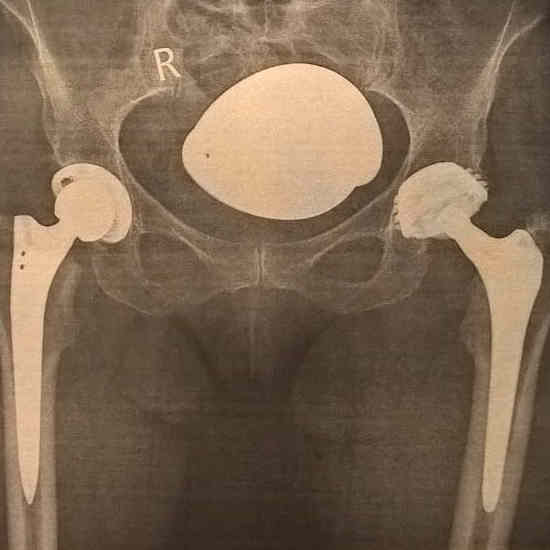

Erfahren Sie mehr über die sympatische Extremsportlerin Claudia Wenning (seit dem 17.07.2021 - vorher Weber), die mit zwei Hüftprothesen sportliche Leistungen erbringt. Bis 2010 war Sie auf den Laufstrecken der Welt unterwegs war und hat sich für die gute Sache mit selbst organierten Läufen eingesetzt. Dabei konnte sich fast 70.000 Euro an Spenden sammeln. Im Jahre 2011 endete die Läuferkarriere vorerst, da eine bis daher nicht erkannte (von Geburt an) Hüftdysplasie festgestellt wurde. Mittlerweile hat Claudia 2 Hüft TEP's und läuft Strecken bis Halbmarathon und ist aber nicht müde sich weiter für andere Menschen einzusetzten. Klicken Sie sich durch Ihre Webseite oder treten Sie mit mir in Kontakt.

Ab 2018 ist Sie mit zwei Hüft TEP's auf den Laufstrekcne bis maximal Halbmarathon, sowie im Triathlon Bereich unterwegs.